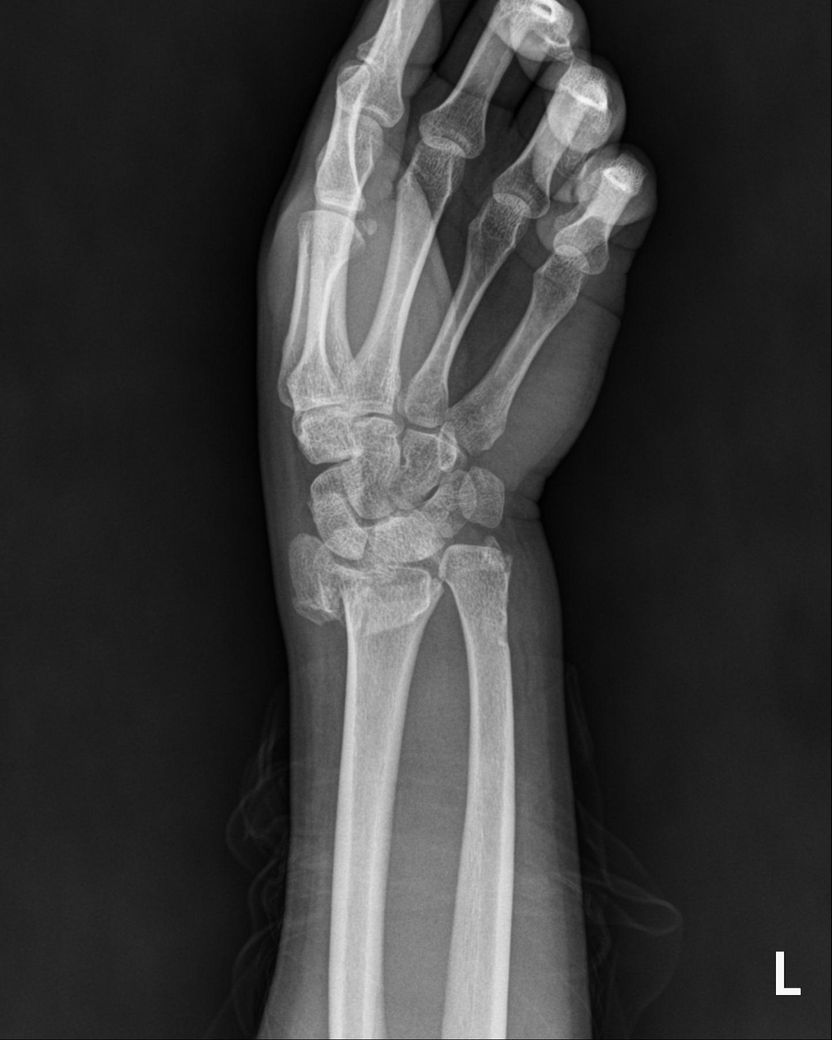

25년 12월에 빙판길에서 넘어져 요골 및 척골 모두 하단의 골절, 폐쇄성 이라는 진단을 받았으며

CT및 엑스레이는 12월 골절 당시 입니다

현재 상황을 종합적으로 보면, 폐쇄성 골절 후 금속 플레이트가 삽입된 상태에서 4월 이후 TFCC 부위 통증이 급격히 악화된 것은 단순한 염증 반응만으로 설명하기 어렵습니다. 골절 후 요척골 관계(distal radioulnar joint, DRUJ)의 정렬 변화, 플레이트 자체에 의한 기계적 자극, 또는 기존 봉합 부위의 재파열 가능성 모두를 고려해야 합니다. 플레이트가 있어 MRI를 아직 시행하지 못하셨다고 하셨는데, 이 부분이 현재 진단 판단의 가장 큰 제한점입니다.